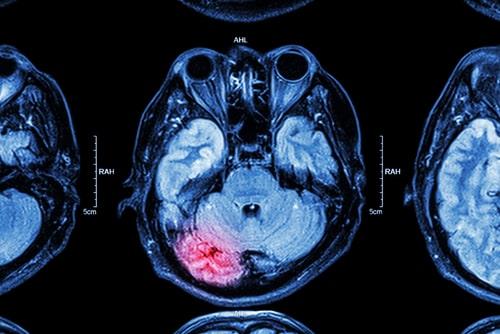

CTE is linked to repeated head trauma, and professional athletes are among the groups with the highest risk of developing it. This disease often gets worse over time and can even lead to dementia. There are four main stages of CTE, with the symptoms associated with these stages generally appearing between eight and ten years after the repetitive brain trauma. The stages are:

Unfortunately, there is no way to diagnose CTE during one’s life and no cure for it. There are tests that can be performed to diagnose CTE, but only during an autopsy. This makes the disease even more devastating. Not only is there no way to get better, but there is also nothing to help you or your loved one understand what is happening and why they are acting the way they are.